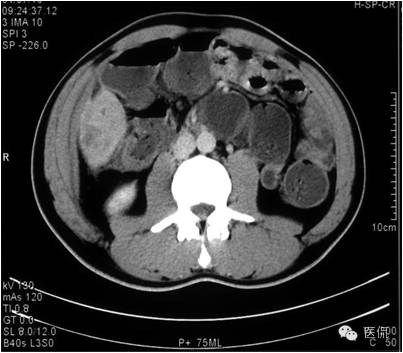

延迟期密度略有降落,但仍有强化,形态不规则。

手术病理诊断:

肝炎性假瘤,侵及周围结肠和腹壁,浸润组织有水肿,粘连。